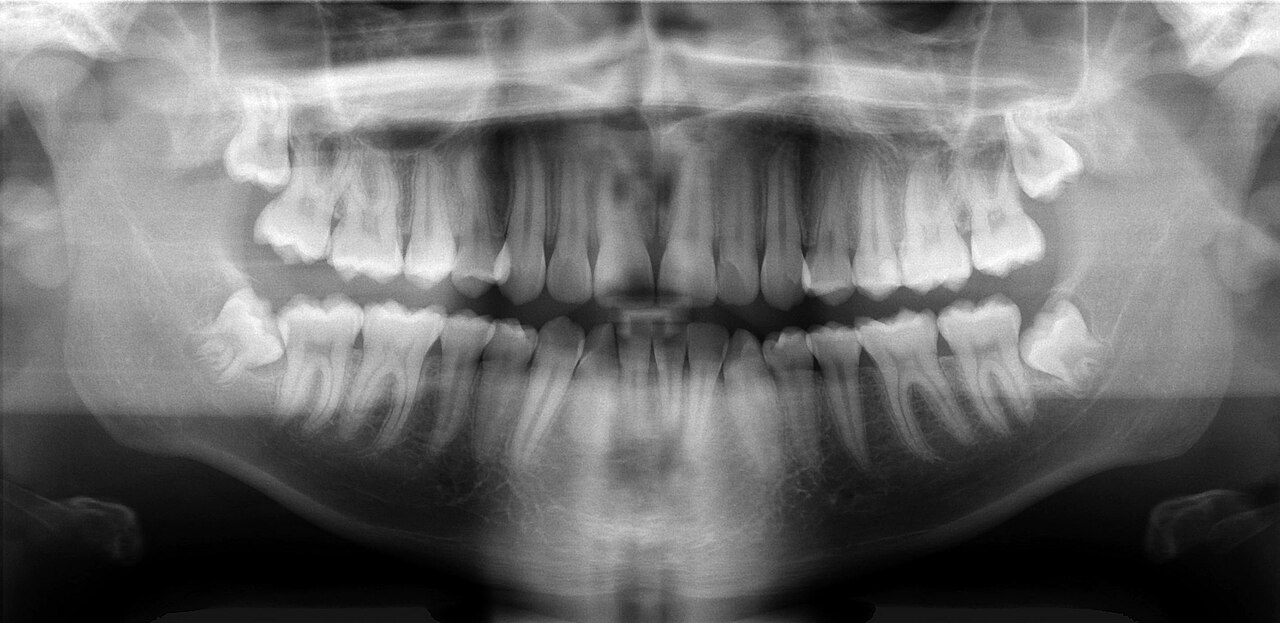

Orthopantomogram (OPG) phantom showing full mandible and maxilla with all teeth, TMJ, sinuses, and surrounding anatomy